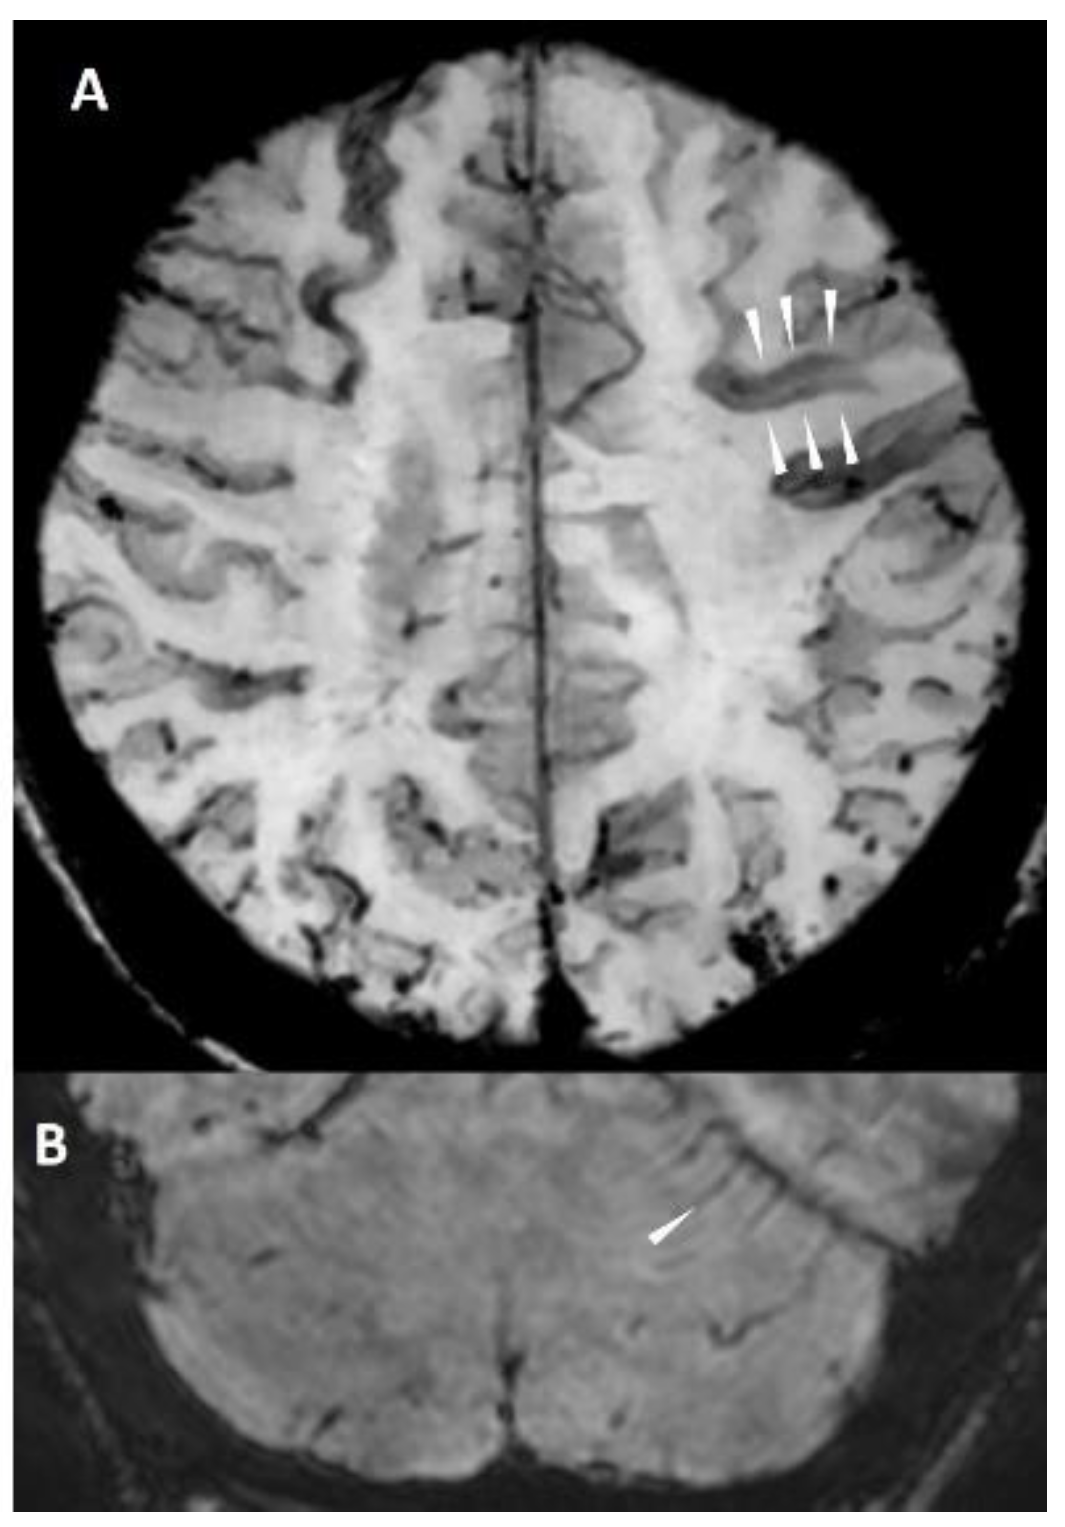

5.1.4. Cortical Superficial Siderosis

5.2. Non-Hemorrhagic Lesions